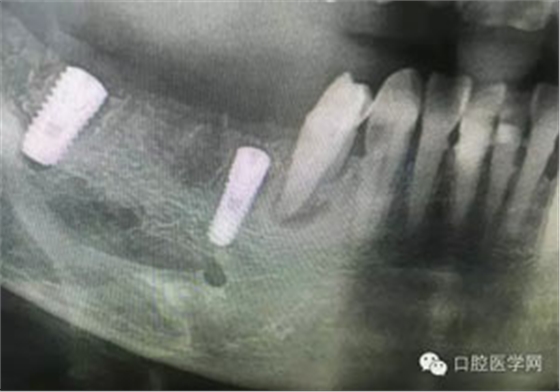

病例1:患者迫切希望保留自己的這一顆牙齒,根尖周陰影比較大,二度松動(dòng).而且旁邊有種植修復(fù)體,和患者溝通好后,治療好后觀察一個(gè)月后冠修復(fù),因?yàn)橛蟹N植的后期修復(fù),所以有了機(jī)會(huì)觀察,術(shù)后三個(gè)月和術(shù)后四個(gè)月,根尖恢復(fù)的還算不錯(cuò),希望能夠繼續(xù)觀察下去.這樣子的病例,做的時(shí)候我們一定要非常的小心,和患者要有充分的溝通以及不同科室的溝通然后決定怎么樣做比較好,假如就是出現(xiàn)了問(wèn)題,到時(shí)候我們也比較好處理些,免得我們自己到時(shí)候不好收?qǐng)觥?/span> 病例2:364647中齲的樹(shù)脂充填,現(xiàn)在樹(shù)脂的充填材料非常之多,有些時(shí)候,我們感覺(jué)有了好的材料我們就可以做出好的修復(fù),可是這是在我們有扎實(shí)的基本功的基礎(chǔ)上的,我們可以沒(méi)有那么好的樹(shù)脂,那么多的顏色選擇,修復(fù)的那么的逼真,但是我們至少要恢復(fù)患者牙齒的功能,將腐質(zhì)去除干凈,薄壁弱尖消除掉,選擇好適應(yīng)癥,給患者以盡可能好的修復(fù)。 來(lái)源于KQ88